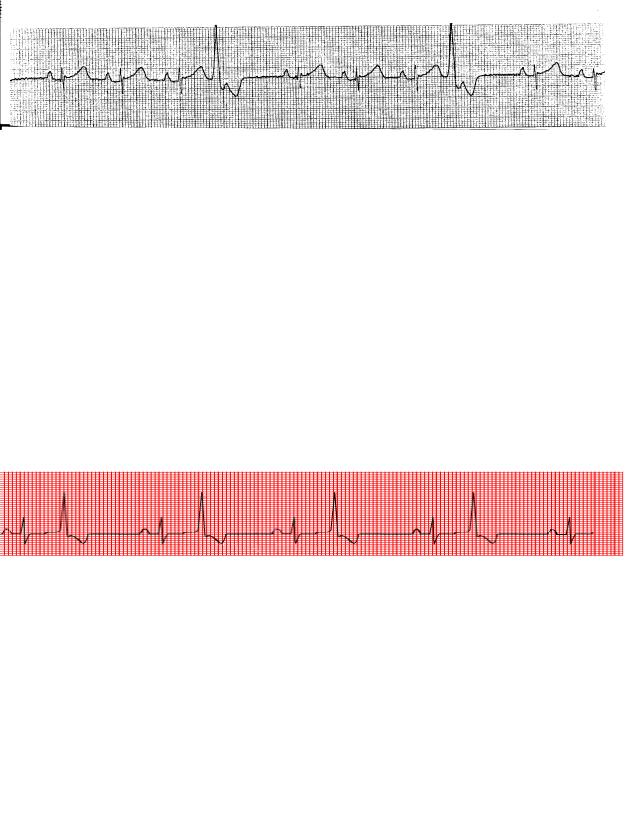

Рис. 3.16. А – вставочная экстрасистола; Б – вставочные полиморфные и полифокусные экстрасистолы

При синусовом ритме, медленным настолько, что после экстрасистолы любого происхождения все структуры сердца успевают выйти из рефрактерного периода к моменту очередного синусового импульса, он нормальным образом распространяется по сердцу. Компенсаторная пауза при этом отсутствует. Экстрасистола оказывается заключенной в нормальный по времени интервал RR (рис. 3.16). Такая экстрасистола называется интерполированной (вставочной).